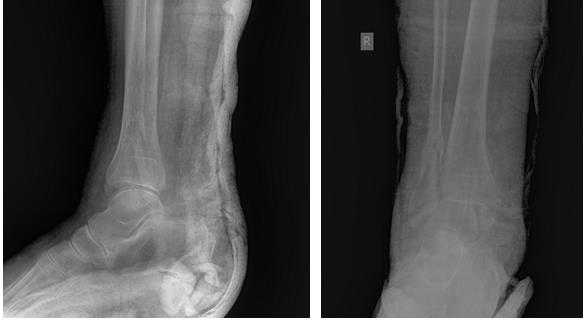

Переломы лодыжек следует дифференцировать с повреждением связок голеностопного сустава. При переломах боль, как правило, локализуется выше, максимальная болезненность определяется при пальпации костей, а не мягкотканных образований. Для постановки окончательного диагноза назначается рентгенография голеностопного сустава в двух стандартных проекциях (боковой и переднезадней). На снимках определяются линии изломов, направление и степень смещения отломков, вид подвывиха и степень расхождения берцовых костей. В сомнительных случаях назначают КТ голеностопного сустава, при необходимости оценить состояние мягкотканных структур - МРТ голеностопного сустава.

Клинический случай 1. Перелом обеих лодыжек с подвывихом стопы кнаружи.

Пациентка Т. 80 лет. Травма за 3 недели до обращения, получила перелом обеих лодыжек правой голени со смещением, подвывихом стопы кнаружи. Обратилась в РТП, выполнена рентгенография, наложена гипсовая повязка. В связи с сохраняющимся выраженным отёком и болевым синдромом обратилась в клинику К+31.

На рентгенограммах в гипсе определяется значительный подвывих таранной кости кнаружи, консолидирующийся перелом нижней трети малоберцовой кости.